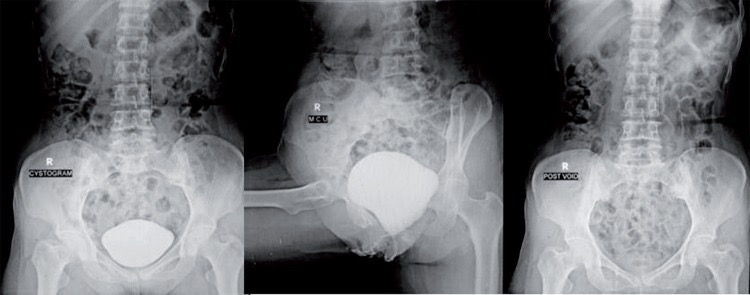

Figure 4. Микционная цистоуретрография показала интактный мочевой пузырь и полное опорожнение мочевого пузыря без утечки контрастного вещества.